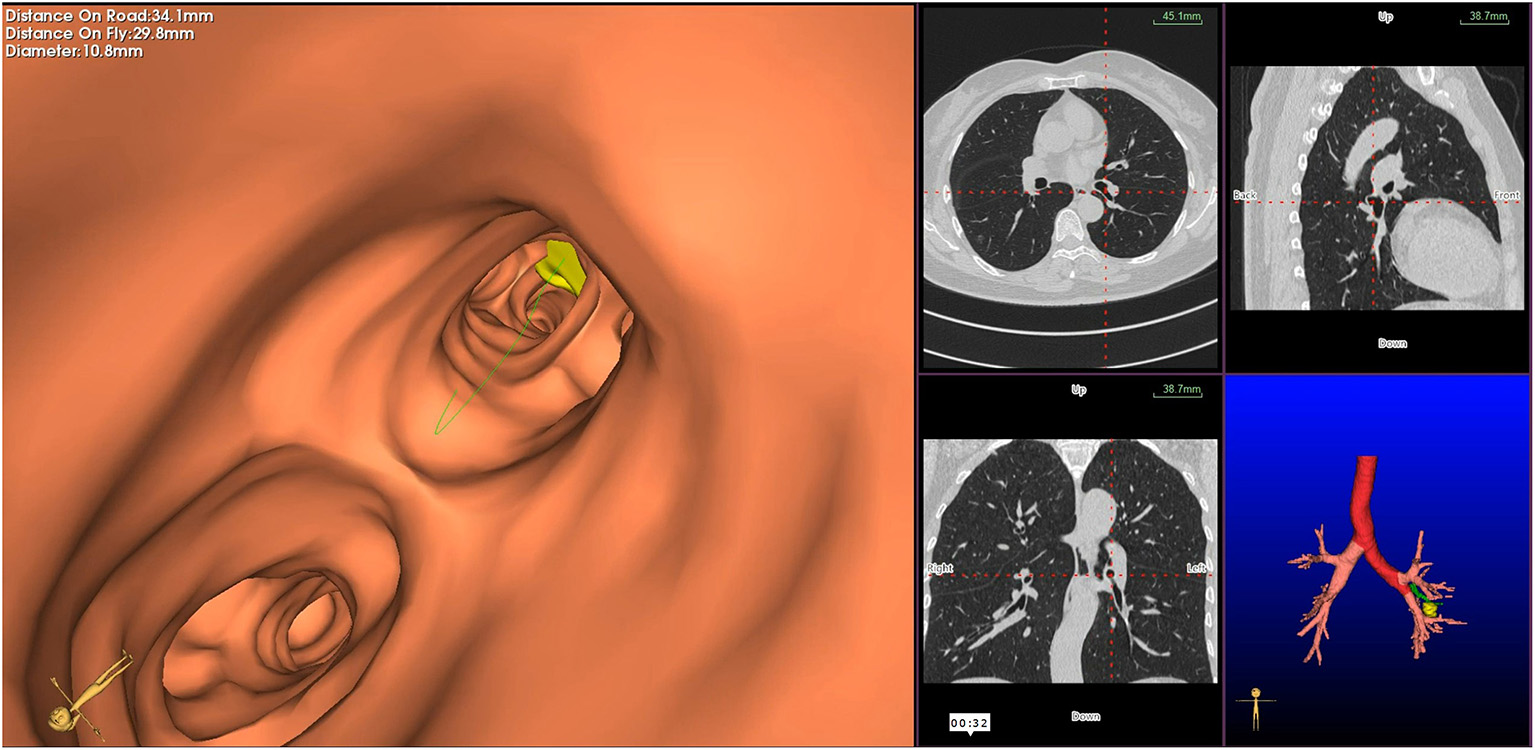

Virtual bronchoscopic navigation is a navigational technique that utilizes data of helical CT to construct three-dimensional virtual images of the bronchial route to guide the bronchoscope to the target lesion (Figure 1). Bf-NAVI® (Cybernet System Inc., Tokyo, Japan) was the first VBN system that was introduced in Japan in 2008, LungPoint® (Broncus Medical Inc., Mountain View, CA, USA) was launched in 2009 in the USA and is now widely used in the USA and European countries (10). DirectPath® (Cybernet System Inc.), which has replaced Bf-NAVI, is used in China by most centers. There are mainly 3 phases of virtual bronchoscopic navigation: planning, guidance, and biopsy. (i) Planning phase: In the planning phase, data from multi-detector chest CT of patients are imported to the computer via VBN software (Figure 2), which automatically creates the virtual bronchoscopic pathway to the target lesion (Figure 3). To obtain high-quality virtual bronchoscopic (VB) images, continuous volume CT data is required. Planning is a pre-bronchoscopy process that is usually done on the same day or days before the intended biopsy. (ii) Guidance phase: The virtual images acquired during the planning phase are used to advance the bronchoscope manually to the target lesion, and the position of the bronchoscope tip can be displayed on the CT images corresponding to the bronchial tree. (iii) Biopsy phase: The choice of procedure to biopsy lesion depends on patient selection and target disease. PPLs can be sampled with flexible bronchoscopy, ultrathin bronchoscopy, and radial endobronchial ultrasound probes (RP-EBUS).

Figure 3

Virtual bronchoscopic image depicting the bronchial route to the target lesion—the green line represents the bronchial route to the lesion, and the yellow circle represents the target peripheral pulmonary lesion.